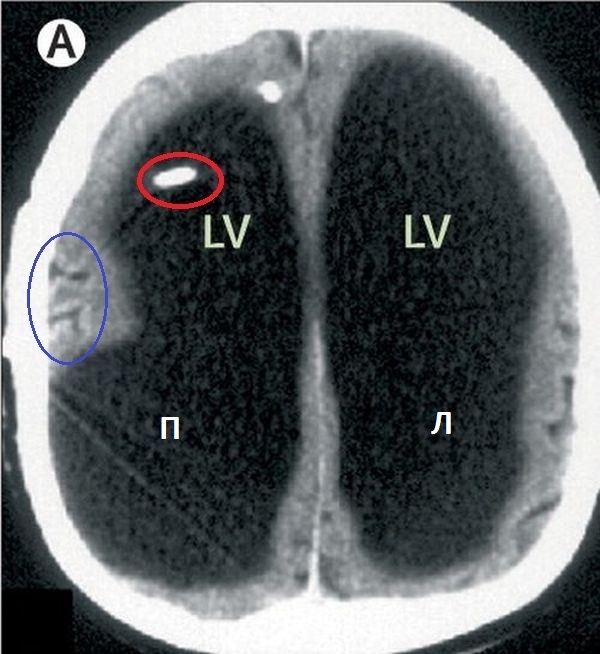

Снимок А: Это КТ-картина головного мозга (аксиальный снимок). LV-боковые желудочки, правый и левый. Красным отмечен вентрикулярный конец шунта. Синим извилины головного мозга, опосредовано это нам говорит об отсутствии отека головного мозга и компенсации процесса.